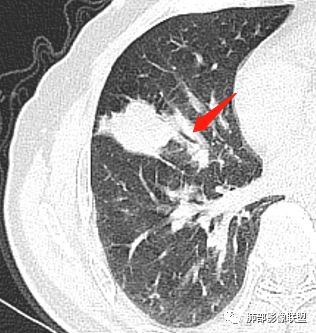

这个支气管是走形通畅,但是壁增厚的。比较符合炎症改变

下面我们看看支气管都在吗?

内侧段是通畅但是受压的

外侧段一开始狭窄

但是远端通畅,所以我认为支气管都没有堵塞,不太可能是鳞癌

病灶明显平直,中央是粘液栓,低密度,分界清楚

支气管进入其中,远端粘液栓

吴婧老师和南边老师都对该病例进行了深入分析。从支气管管壁的增厚,支气管狭窄后扩张,支气管粘液栓,病灶形态,到病灶不均匀强化及坏死彻底,到周边病灶及肺组织空气的潴留,加之纵隔内淋巴结肿大伴钙化等等,都支持慢性炎性病灶,尤其是结核。

现在小编来增加一个炎性另一个征象,是我们王兆宇老师原创的----就是墨西哥仙人掌征。

墨西哥仙人掌征---结核        影像上结核灶,粗大的均匀枝干,推测是支气管囊状扩张引起的,在非支气管区,形成圆形坏死囊群;如果这些坏死比较稀薄,又遇到扩张支气管,就会形成粗大的“墨西哥仙人掌”。结核引起的支气管近端炎症纤维化,可以造成支气管阻塞,从而将干酪样坏死物封堵在管腔内。仙人掌主干内部应该是干酪为主,稀薄的,具有流动性,时间久了会出现钙化。

结核坏死与鳞癌鉴别有一点是结核坏死没有方向性,鳞癌有。鳞癌靠近支气管近端部分,血供容易维持,不易坏死,所以坏死靠外侧。而结核干酪样坏死,把一定体积的流动性坏死物,包裹起来,什么形状最省料?坏死物包裹,表面积最省的自然是圆球形,而遇到支气管,坏死物一多,就把支气管撑大了。包裹物是就地取材,扩张的支气管就成了包裹结构。